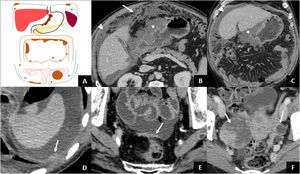

By penetrating the peritoneal layers, GAs can spread within the peritoneal cavity. Fifty percent of patients with tumours infiltrating the muscle layer or beyond (≥ T2) present with peritoneal spread at diagnosis1. Evidence of peritoneal metastatic involvement means that the disease is incurable, so a thorough assessment of the peritoneum is essential. Imaging findings that are indicative of peritoneal carcinomatosis include ascites (the most common finding), nodules or plaques on the peritoneal surface, intra-abdominal fat stranding, and irregular thickening and enhancement of the peritoneum40. Special attention should be paid to the dependent portions of the peritoneal cavity, such as the pouch of Douglas or the rectovesical space, or areas where a large amount of peritoneal fluid is absorbed (subdiaphragmatic surface and omentum), as ascites favours subperitoneal dissemination to these regions (Fig. 7)41,42. Ovarian metastases from AG (Krukenberg tumours) are usually of the signet ring cell histological type and may be due to intraperitoneal spread of AGC or lymphatic spread when there is no serosal invasion43. In patients with tumour recurrence after surgery with curative intent, the most common type of recurrence is peritoneal spread44.

Transperitoneal dissemination. A) Illustration of a GA with transperitoneal spread presented with peritoneal carcinomatosis (subdiaphragmatic and pelvic implants, plaque of pelvic peritoneal thickening, omental cake) and Krukenberg tumour on the left. The arrows point to the direction of the ascites. B and C) Locally advanced antro-pyloric GA (asterisks), diffuse type with signet ring cells, with peritoneal carcinomatosis: ascites (arrowheads) and striking omental thickening or omental cake (arrow). D) Left subdiaphragmatic peritoneal implant (arrow) and ascites indicating tumour recurrence of the operated GA. E) Peritoneal thickening in hyperintense plaque (arrow) due to peritoneal carcinomatosis. F) Diffuse type GA with signet ring cells with bilateral Krukenberg tumour (arrows).